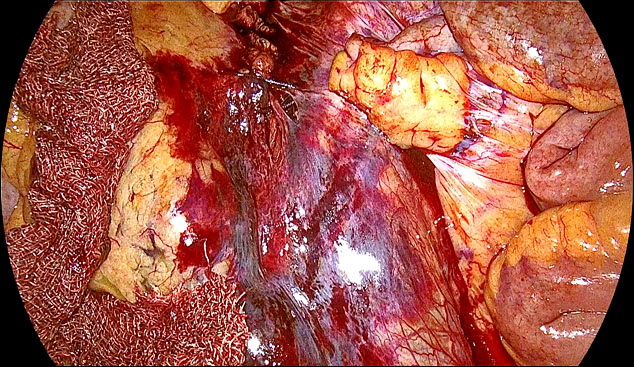

Vessel injury during dissection, especially with monopolar cautery/scissors (Figure 16A), can be managed if venous, by applying pressure with a gauze, and, if small, by holding it with an atraumatic dissector and the use of bipolar in bursts (Figure 16B).

In the event of uterine artery bleeding during dissection, once identified, the laparoscopist should remain calm. CO₂ insufflation and suction at pressures below 300 mmHg help maintain pneumoperitoneum. The bleeding vessel should be carefully grasped with bipolar cautery forceps or another appropriate instrument (Figure 17) after adequate dissection. Occasionally, the presence of a gauze piece can help localize the bleeding source. It is important to avoid forcefully grasping the bleeding area, as the uterine artery lies above the ureter, which in turn is above the uterine vein. If the bleeding originates from the vein, bipolar cautery may inadvertently damage the ureter. Once hemostasis is achieved, hemostatic agents such as Surgicel may be applied, although they are often unnecessary.

(a) |

(b) |

(c) |

17

(a) Right uterine artery active bleeding after removal of the uterus. (b) Stabilizing the bleeder by atraumatic forceps with suction. (c) Stabilized tip of the vessel coagulated with bipolar cautery forceps.